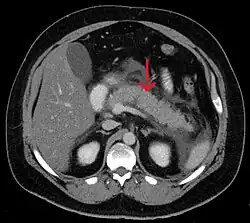

Acute exudative pancreatitis on CT scan

A contrast-enhanced CT scan is usually performed more than 48 hours after the onset of pain to evaluate for pancreatic necrosis and extrapancreatic fluid as well as predict the severity of the disease. CT scanning earlier can be falsely reassuring.